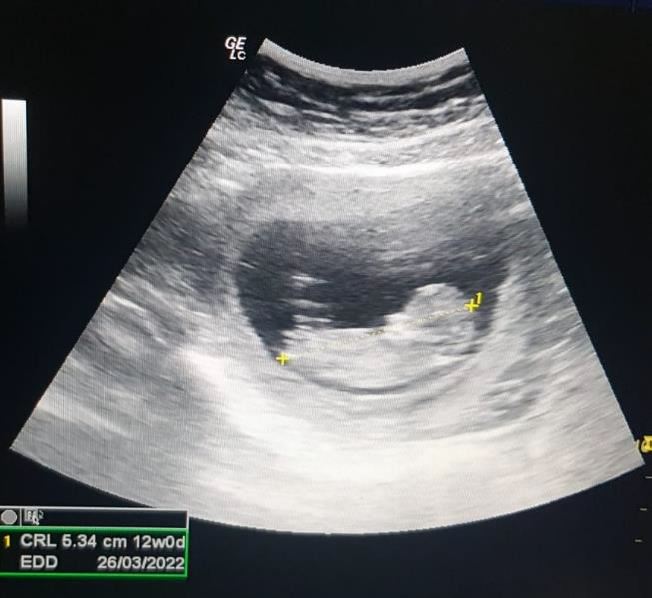

Two months following the procedure, the patient came with positive home pregnancy test. Ultrasound examination show a gestational sac with mean sac diameter 16 mm.Two months later, the pregnancyshowed a positive fetal node and heart beat(Figure 3). Antenatal care was scheduled asroutine care for pregnancy.